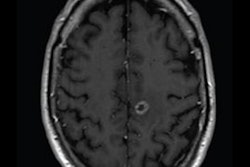

The U.S. Food and Drug Administration (FDA) has granted breakthrough status to Darmiyan's artificial intelligence (AI)-based software, BrainSee, which detects Alzheimer's disease from MRI scans.

BrainSee detects Alzheimer's disease at the early stage of mild cognitive impairment using a brain MRI. The scan does not require an injection or radiation. The software will enable clinicians to select patients who are in the early stages of neurodegeneration for clinical trials, paving the way for potential new therapies and treatments.